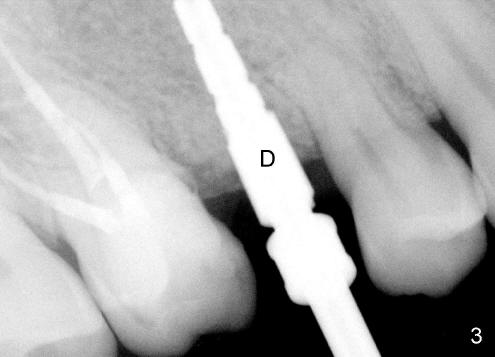

范女士牙齿不好,终于决定做植牙修复,要求先做前面牙齿,尤其是上颌第二双尖牙(图一:左右5)。第一次植入两个种植体(图一:左上5,7,同时拔牙),很顺利,即刻植牙好比顺藤摸瓜。第二次准备种右上五号牙,那里骨头高度绰绰有余(图一),好像也是小菜一碗。